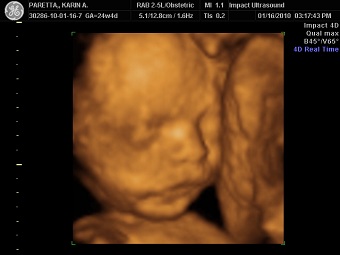

24+4 with my son Chat Icon

I had a 2D/3D sono last night with my daughter (17 weeks) and it was near impossible to see anything.

Image Attachment(s):

Message edited 8/17/2012 12:11:21 PM.